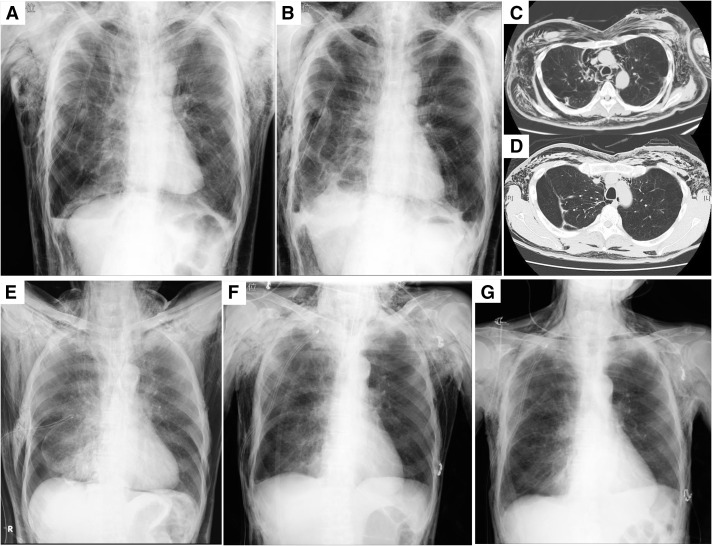

Severe subcutaneous emphysema that is refractory to chest tube drainage can result in significant patient discomfort, airway compromise, and hemodynamic instability. Various interventional approaches, including subcutaneous drain insertion and the blowhole technique, with or without negative pressure wound therapy (NPWT), have been proposed to manage this condition. In this case series, we describe 10 patients who developed severe subcutaneous emphysema following surgery or pneumothorax and were treated using the blowhole technique, with or without NPWT. A Wound Protector/Retractor XXS or LapProtector was used to maintain the patency of the blowhole, facilitating continuous decompression. In cases with more extensive emphysema, the application of NPWT led to rapid respiratory improvement, thereby enabling additional invasive interventions to address the underlying pulmonary air leak. These findings highlight the potential utility of a structured approach incorporating NPWT for the management of severe subcutaneous emphysema, particularly in cases refractory to conventional chest tube drainage.